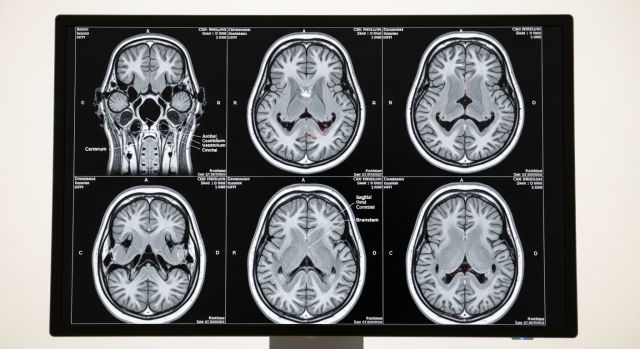

초기 발견 후 어떤 검사를 받나요

치매안심센터에서 1차 선별검사(MMSE, CIST)를 무료로 받을 수 있습니다. 이상 소견이 있으면 협력 병원에서 신경인지기능 정밀 검사, 뇌 MRI·CT, 혈액 검사를 통해 원인을 정확히 감별합니다.

알츠하이머 확진을 위한 아밀로이드 PET 검사나 뇌척수액 검사는 필요에 따라 추가로 진행됩니다. 최근에는 혈액 한 번으로 알츠하이머 원인 단백질을 측정하는 혈액 바이오마커 검사도 도입되고 있습니다.

치매 진단을 받더라도 초기라면 약물 치료를 즉시 시작해 진행을 늦출 수 있으며, 경도인지장애 단계에서 발견하면 일부에서 정상으로의 회복도 가능합니다. 두려움보다는 빠른 행동이 훨씬 중요합니다.